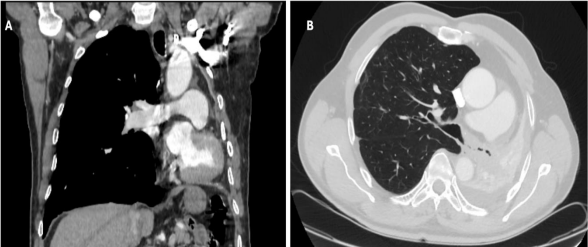

A 64-year-old gentleman underwent an upper left lobectomy with radical lymphadenectomy by left lateral thoracotomy and had an adjuvant chemotherapy for a pT2bN0 squamous lung carcinoma in 2018. He was admitted in our department with a proven recurrence in the remaining lower left lung and invasion of the main bronchus up to the carina. Enhanced CT-Scan revealed a complete left lower lung atelectasis and left shifted mediastinum (Fig 1). An intrapericardial left completion pneumonectomy, carinal resection and anastomosis between the proximal trachea and the distal right main bronchus stump were performed only through a left posterolateral thoracotomy. Anesthetic management consisted in thoracic epidural analgesia, an internal jugular central venous line, and a radial arterial catheter. Anesthesia was induced using propofol, ketamine, fentanyl, and rocuronium. The patient was intubated with a 37 Fr left double-lumen endotracheal tube (ETT) and maintained on propofol TCI to avoid sevoflurane contamination in the operating room. Thoracotomy was performed away from the previous scar, entrance in the pleural cavity was carefully carried out, pericardium abutting at the chest wall, hilar structures were individualized within the pericardium, left pulmonary artery and the inferior pulmonary vein were stapled, the bronchial tree was meticulously dissected with a digital dissection of the distal tracheal and right tracheal tree and with simultaneous lymphadenectomy. Tracheal was sectioned one cartilage above the carina and the right main bronchus between the first and the second cartilage. The specimen was extracted, a cross-field tube 5.0 mm cuffed endotracheal tube was used to intubate in the right bronchial tree and running suture was performed between trachea and  right main bronchus with 3.0 PDS. The patient was immediately extubated with less than 12 hours stay in intensive care unit. He underwent active physiotherapy, he had pain killers and preventive anticoagulation (Fig 2). He presented atrial fibrillation (on day 2) that was converted with medication. The control bronchoscopy performed on day 7 was satisfactory (Fig 3), he was discharged the same day. The definitive histopathology revealed a pT4N0M0 R0 squamous carcinoma.

Figure 2